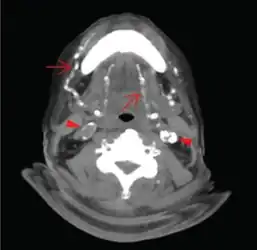

Axial CT slice at the level of C2-C3 soft tissue window setting setting. Extensive calcifications of the bilateral lingual and facial arteries are noted (arrows) as well as calcific plaques at bilateral carotid tree area (arrow heads).